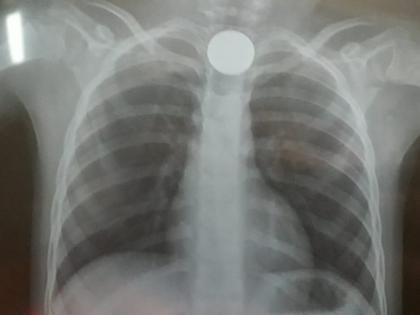

शहरातील माजी उपनगराध्यक्ष संजय लालबिगे यांचा पुतण्या दक्ष (वय ४ वर्ष) याने मंगळवारी(दि २९) सायंकाळी मोबाईलवर खेळता खेळता दोन रुपयांचे नाणे गिळले.त्यामुळे त्याला श्वास घेण्यास काही प्रमाणात त्रास जाणवु लागला.तसेच मळमळ वाढल्याची तक्रार त्याने पालकांकडे केली.त्याच्या पालकांनी तातडीने डॉ. राजेंद्र मुथा यांच्या रुग्णालयात बालकाला दाखल केले.यावेळी तपासणी केल्यानंतर डॉ सौरभ मुथा यांनी एक्सरे काढत नाणे नेमके कुठे अडकले आहे,याची माहिती घेतली.त्यानंतर त्यांनी तातडीने भुलतज्ञ डॉ. अमर पवार, डॉ.वैभव मदने यांना या प्रकाराची माहिती दिली.त्यानंतर या डॉक्टरांनी मिळुन दुर्बिणीच्या सहाय्याने अन्ननलिकेत अडकलेले नाणे काढले.त्यानंतर दक्षचा त्रास कमी झाला.तसेच पालकांनी सुटकेचा नि:श्वास सोडला.

गेल्या दोन दिवसांत मुलांनी नाणे गिळल्याच्या दोन घटना घडल्या आहेत.काही मुलांच्या नाकात शेंगदाणे,फुटाणे अडकल्याचे प्रकार घडतात.शिट्टी गिळण्याने त्रास झालेली बालके रुग्णालयात आलेली आहेत.काल दक्ष याचा श्वास कोंडत होता,त्याला उलटी होण्याचा त्रास होता.दुर्बिणीच्या सहाय्याने १५ ते २० मिनिटांत त्याच्या अन्ननलिकेत अडकलेले नाणे काढण्यास सुदैवाने यश आले.त्याला घरी सोडण्यात आले आहे.त्याची प्रकृती स्थिर आहे.